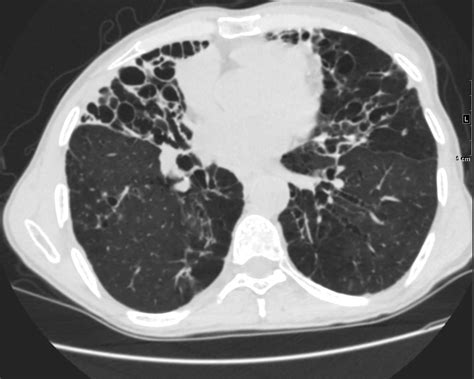

The syndrome was historically characterized in older women who chronically suppress their cough. By holding in their coughs to maintain social etiquette, these individuals inadvertently allow mucus, bacteria, and debris to accumulate in the airways of the lungs, specifically the right middle lobe and the lingula (part of the left upper lobe). This stagnation creates the perfect environment for NTM to colonize and cause chronic disease.

• High-Resolution Computed Tomography (HRCT) Scans: This is the gold standard for visualizing the characteristic bronchiectasis and nodules in the middle lobe and lingula.